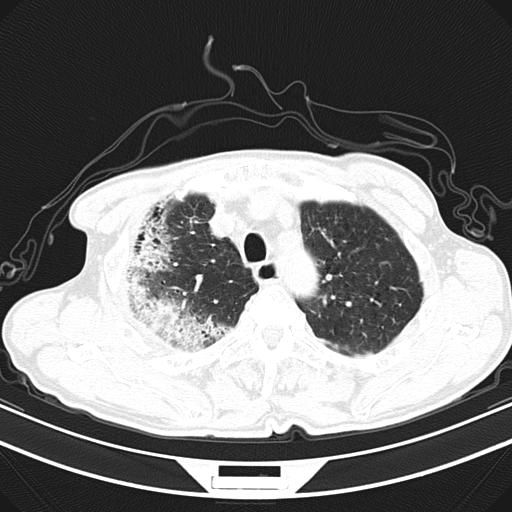

男,70,发烧咳嗽咳痰10余天,查痰结核菌阴性。否认以前有肺病史。治疗10天后症状减轻。 img]/upload/forum/2009/12/302117469692.jpg[/img]

影像所见:右上肺见一巨大厚壁空洞,内壁欠光整,右上肺广泛斑片状、大片状模糊阴影。

影像所见:右上肺见一巨大厚壁空洞,并见分隔,内壁欠光整,右上肺广泛斑片状、大片状磨玻璃阴影。